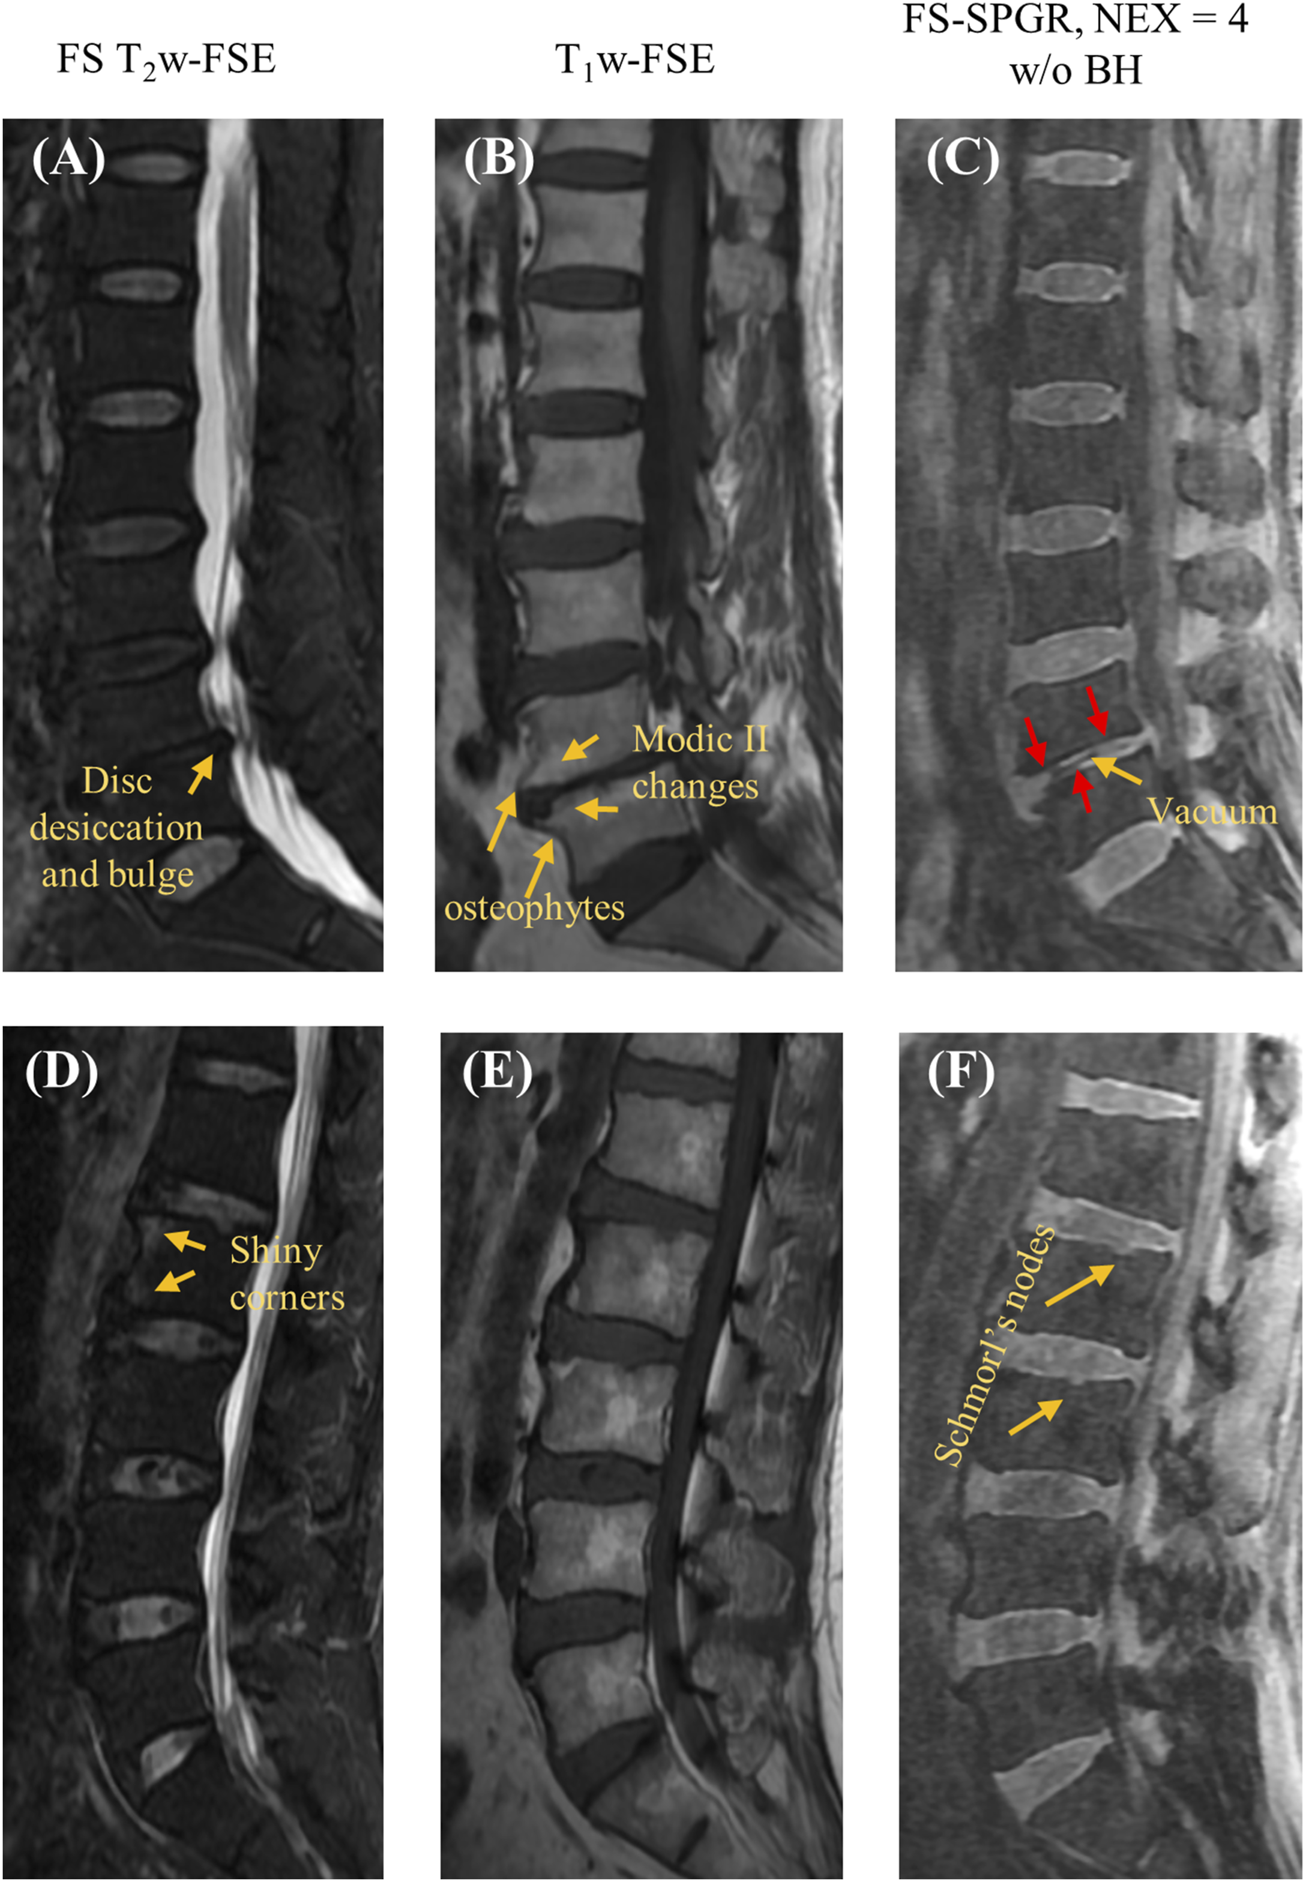

Figure 3 shows the FS-SPGR images (free breathing, NEX = 4) along with clinical images acquired from two different patients (67 years old, female and 61 years old, male, respectively) with lower back pain. For the first patient, Figures 3A–C exhibit degenerative disc disease at L4-5, marked by disc bulging, desiccation, vacuum phenomenon, fatty marrow replacement (Modic II changes), and marginal osteophytes. The arrows indicate areas of CEP loss, greatest at the anterosuperior aspect of L5. For the second patient, Figures 3D–F reveal shiny corner lesions that are most prominent at the anterosuperior and anteroinferior aspects of the L2 vertebral body. The proposed FS-SPGR sequence depicts small Schmorl’s nodes from L1 through L3, while the superior L1 nodes have preserved CEPs. In contrast the superior L2 and L3 levels exhibit disrupted CEPs covering the nodes.

FIGURE 3

Clinical FS T2w-FSE (A,D) and T1w-FSE (B,E) images as well as 3D FS-SPGR (free breathing, NEX = 4) (C,F) images acquired from two patients with lower back pain (first row: 67-year-old female; second row: 61-year-old male). The abnormal CEP regions are indicated by red arrows in panels (C,F) while other pathologies like disc desiccation [panel (A)], Schmorl’s nodes [panel (F)], Modic II changes [panel (B)] are pointed by yellow arrows.